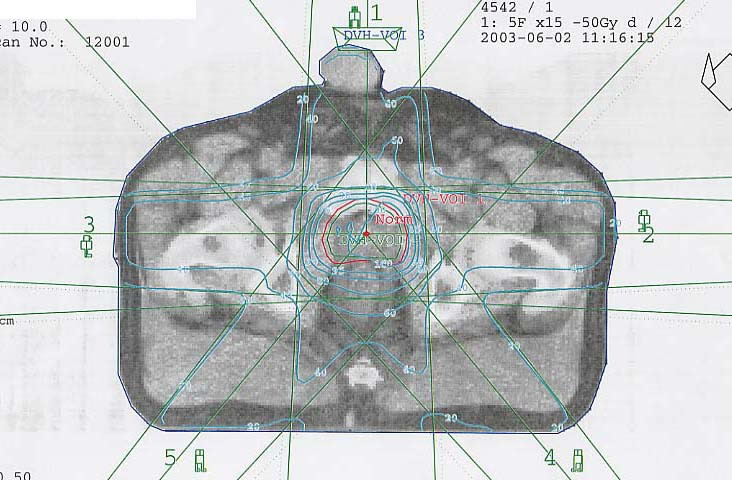

Prostatakarzinom: Bestrahlungsplan